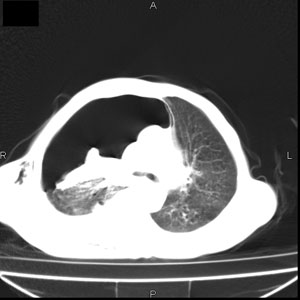

患者男,77岁,于3日前从树上摔下,头部查ct示蛛血,硬膜下出血,上腹部ct未见明显异常,右侧胸腔积液,左侧如常。肺部拍片示右侧肋骨多发骨折住院后今日来查肺部ct,我看到的是1。右侧胸腔血气胸并右肺上叶,中叶压缩性肺不张,2。右肺下叶肺挫伤并多发肋骨骨折,肌内及皮下积气3。左侧少量胸腔积液,我想请教的是3天前左侧胸腔里没有积液今天怎么出现了呢,是什么原因呢?请讨论。